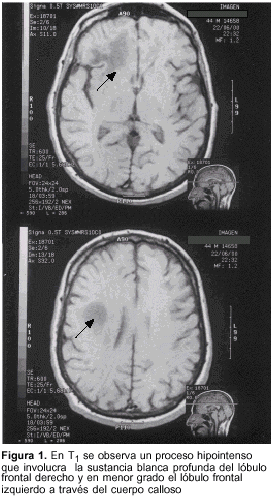

Paciente de sexo masculino, 44 años, diestro, infección por VIH detectada en marzo de 1997, en tratamiento antirretroviral (desde dos años atrás) con AZT, 3TC e indinavir. En agosto de 1999 presentaba una población linfocitaria con CD4 inferior a 160 elementos/mm3. En mayo de 2000 comienza con un síndrome confusional, alteraciones conductuales y cefalea moderada. A los pocos días de su ingreso se percibe pérdida de fuerza de sus miembros izquierdos y alteraciones del habla que se agravaron en el curso de los días. No se detecta fiebre. El examen mostraba un paciente irritable, con desorientación temporal y espacial, tendencia al mutismo, síndrome tónico frontal bilateral predominando a derecha. No se detectó síndrome meníngeo ni fiebre. La TC craneal en fase de estado mostró una lesión frontal derecha y de cuerpo calloso, con compromiso menor del lóbulo frontal izquierdo que incidía especialmente sobre la sustancia blanca, sin efecto de masa y con realce con el contraste. La RM encefálica delimitó con mayor exactitud las lesiones observándose lesiones de baja señal en T1 y de aumento de señal en T2 y en densidad protónica en las topografías señaladas (figuras 1, 2 y 3). El estudio de LCR mostró un citoquímico normal, el estudio por PCR fue negativo para el grupo herpes (HVS 1; HVS 2, CMV, EBV, HH6, VZ), y para virus JC. Se resuelve practicar biopsia estereotáxica. El estudio de dicha pieza con técnica de PCR mostró su positividad para el virus JC. La anatomía patológica convencional mostró: "En las seis tomas biópsicas, imágenes microscópicas con alteraciones de LMP con desmielinización. Hay acúmulos de histiocitos de citoplasmas microvacuolados por fagocitosis de restos mielínicos lipídicos (figura 4). La desmielinización de la sustancia blanca queda en evidencia por la técnica de Luxol que muestra palidez del azul con que tiñe la mielina. Existe moderada astrogliosis con astrocitos de aspecto bizarro símil neoplásicos, con núcleos grandes, algunos multilobulados que no se acompañan de aumento de densidad celular (figura 5). La oligodendroglía muestra una cariomegalia hipercuomática y algunos de ellos tienen gruesas inclusiones intranucleares acidófilas 'en vidrio esmerilado' que contienen el antígeno viral (figuras 5 y 6). Hay escaso o nulo exudado inflamatorio perivascular linfo-plasmocitario".